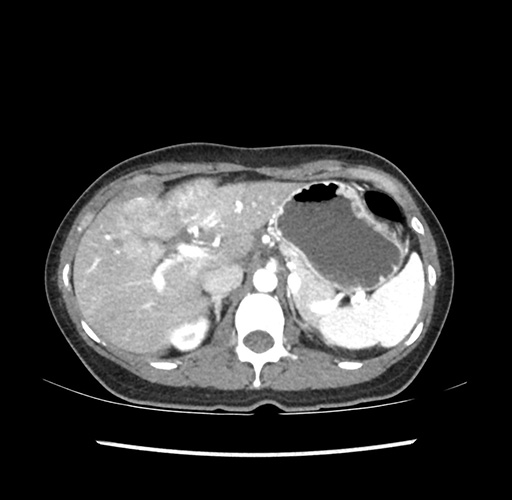

Imaging Analysis

Look through the patient's CT scan to identify any areas of concern for the necessary procedure.

Based on your CT findings, which issue(s) would give reason for "planned slowing down moment(s)" in this case?

Considering a standard left lateral sectionectomy procedure, what step(s) of the operation would you do differently in this case ?